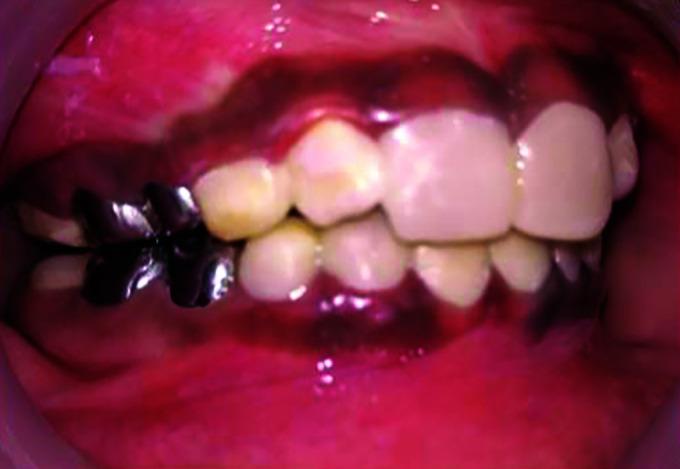

Amelogenesis imperfecta (AI) is an inherited dental condition affecting enamel, which can result in significant tooth discoloration and enamel breakdown, requiring lifelong dental care. Distal renal tubular acidosis (dRTA) is a condition in which the kidneys are unable to acidify the urine to a pH < 5.5 in the presence of systemic metabolic acidosis. Management of AI and dRTA patients requires both medical and dental expertise to achieve long-term successful results. The aim of this paper is to present the dental management of a child with AI and dRTA.

牙釉质发育不全(AI)是一种影响牙釉质的遗传性牙齿疾病,可导致牙齿严重变色和牙釉质损坏,需要终身牙齿护理。远端肾小管酸中毒(dRTA)是一种在全身性代谢性酸中毒情况下,肾脏无法将尿液酸化至pH < 5.5的病症。对AI和dRTA患者的管理需要医学和牙科专业知识,以取得长期的成功结果。本文的目的是介绍一名患有AI和dRTA儿童的牙科管理情况。